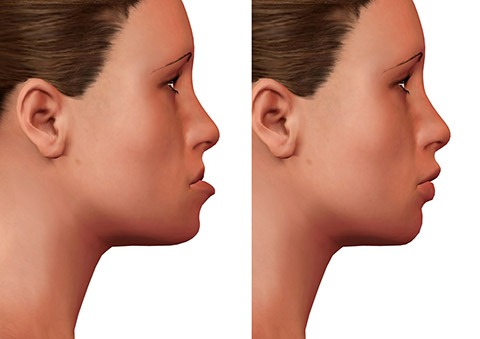

www.advancedfaces.comjaw orthognathic

www.advancedfaces.comjaw orthognathic